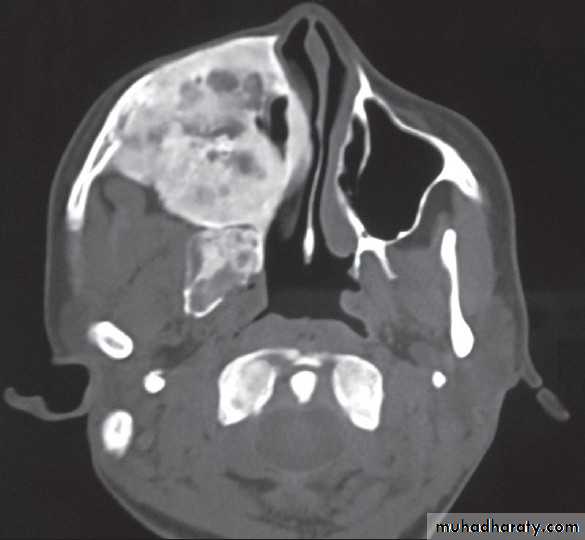

FIBROUS DYSPLASIA

Axial CT shows radiopaque mass oblitearating maxillary sinus and nasalcavity on the right sideAmeloblastoma(ADAMANTINOMA)

Arises from odontogenic tissueLocally aggressive

Invades maxillary sinus

Rx :surgical excision